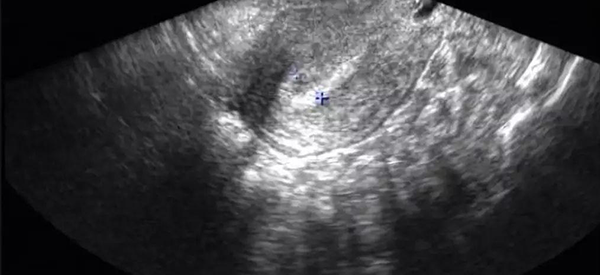

3、C型:常见于黄体期,即排卵后到下次月经来潮前,内膜厚度约10-14mm。为均质强回声,无宫腔中线回声,此时“三线征”消失。

内膜呈c型是不利于受精卵着床的。C型内膜呈均质强回声,三线征消失,这种类型的内膜常见于黄体期。如果是C型内膜,可能子宫厚度是比较厚的,也就是说这个子宫内膜的厚度发生了损害。建议进一步的进行B超检查,看看具体的厚度,如果此时子宫的厚度与正常的厚度相比不超过一公分,那么对受精卵着床就没有太大影响。